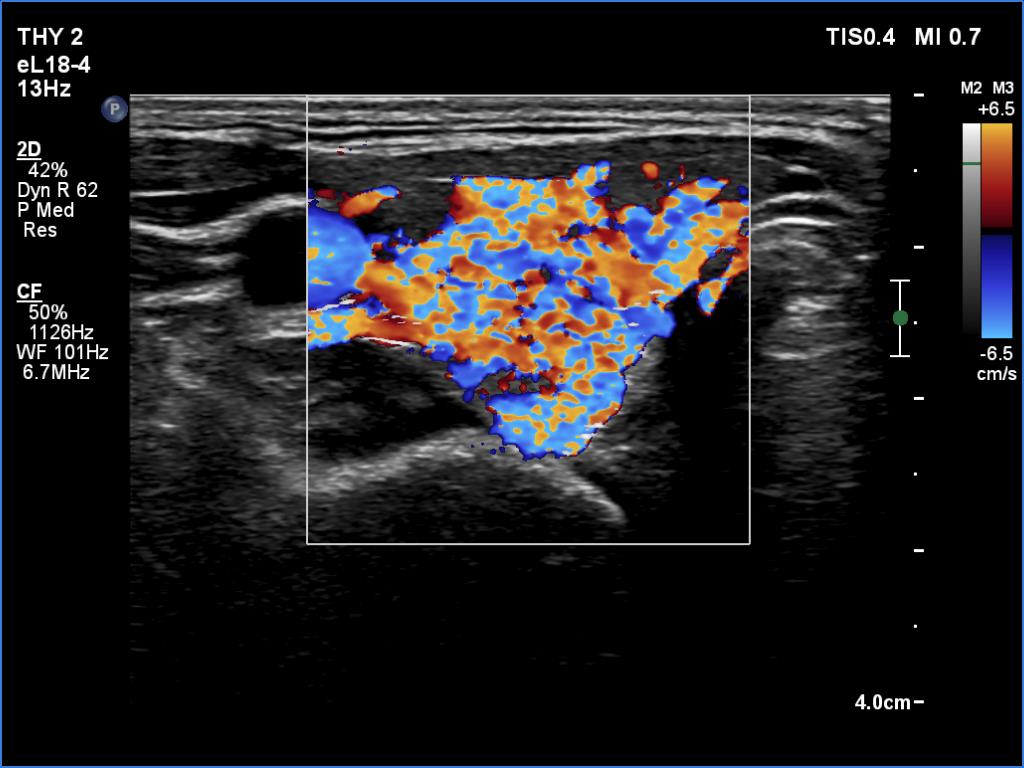

Right lobe, color Doppler mode

This is the usual course of Graves' disease regarding the change in echo pattern - before, during and after the activity of the autoimmune process. The only exception is the change in the size of the thyroid. In most cases, the thyroid increases during the activity of the disease, then returns to normal. However, in this patient the age counts: at the first examination, the patient was only 15-year-old.

- There are two situations in Graves 'disease where circulation is increased. At the stage of disease activity and when hypothyroidism is observed with medication. In the former case, the blood flow is almost always increased, in the latter it can be decreased and increased.